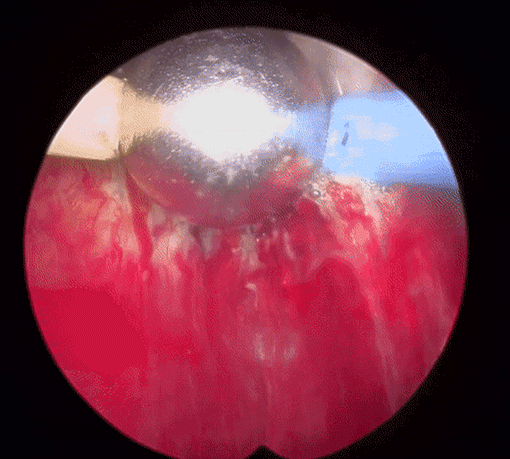

플라즈마 기화술 치료 환자 케이스

주요 증상빈뇨, 야간뇨, 급박뇨

전립선 크기약 80g

과거력전립선 비대증 문제로,약물치료를 해왔으나 증상이 호전되지 않음

시술방법플라즈마 기화술 시행